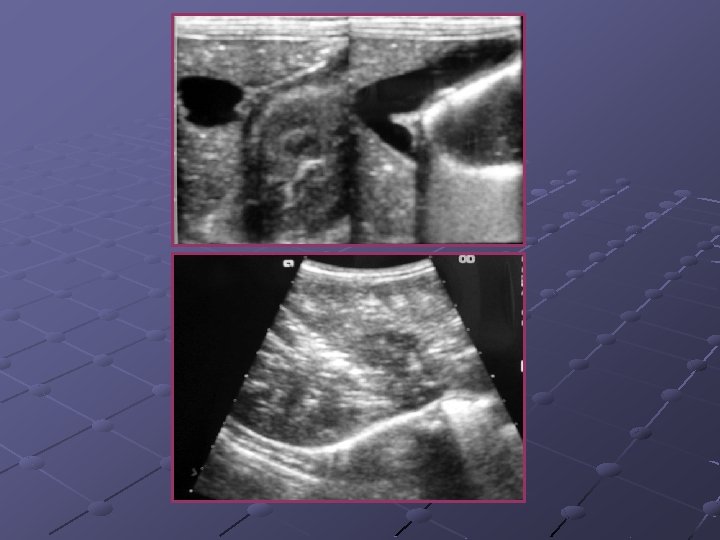

Cas n° 5 17 mois Histoire médicale antérieure = o Pleurs, douleurs abdominales

3, 7 x 2, 8 cm Depuis le rectum hypochondre gauche

INVAGINATION INTESTINALE AIGUE (IIA) Télescopage et penetration d’ un segment intestinal dans le segment d’ aval. Urgence diagnostique et thérapeutique: compression vasculaire ischémie et nécrose Nourrisson ( 80 % entre 6 mois et 2 ans ). Maximum entre 4 et 12 mois (I). Avant 3 mois ou après 5 ans (II). Prédominance masculine ( 3 G/2 F).

Idiopathique ( 90% des cas ): adénolymphite mésentérique(caractère saisonnier ) Secondaire: lymphome digestif, meckel, duplication digestive , polype , purpura rhumatoïde , troubles fonctionnels post chirurgicaux , impactions digestives ( mucoviscidose. . ) Formes anatomiques: iléo-iléale n iléo-colique n Appendico-colique n colo-colique n diam. boudin < 20 mm diam. boudin > 25 mm Diagnostic = échographie et non l’ASP Traitement: - Lavements (air, hydrosoluble, eau) - Chirurgie Contre-indications des lavements: péritonite, choc